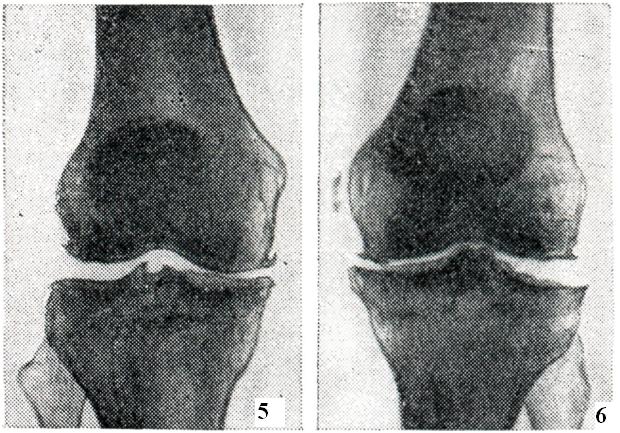

Клинико-рентгенологически можно выделить три стадии в течении артроза. Первая стадия характеризуется незначительными изменениями. Происходит едва заметное сужение суставной щели, особенно в местах наибольшей функциональной нагрузки (например, в латеральном отделе щели тазо-бедренного сустава и в медиальном отделе щели коленного сустава), и появляются незначительные костные разрастания, преимущественно по краям впадины сустава (рис. 5).

Вторая стадия отличается более выраженными изменениями (рис. 6). Сужение суставной щели становится хорошо видимым. Параллельно с изменениями суставной щели определяется перестройка суставных поверхностей. Поверхности эпифизов костей деформируются, уплощаются и становятся неровными; костные разрастания достигают значительных размеров и приводят к деформации суставных концов костей. Особенно резко это бывает выражено в тазо-бедренном суставе: головка бедра уплощается, значительно увеличивается в поперечнике и приобретает грибовидную форму. На характер деформации суставных концов костей влияет и статико-функциональная нагрузка на определенный сегмент конечности, в результате чего меняется конфигурация не только головки, но и впадины сустава (например, псевдопротрузия вертлужной впадины, уплощение суставной поверхности лопатки, болынеберцовой кости и так далее). Деформация суставных поверхностей сопровождается нарушением конгруэнтности, вплоть до развития подвывихов и вывихов в суставе. Нарушение взаимоотношений между суставными отделами костей влечет за собой перераспределение линий статико-функциональных нагрузок, что в свою очередь ведет к развитию деформации по типу coxa vara, humerus varus, дугообразному искривлению костей и так далее.

Информация об Ordo Deus Перейти в оглавление сайта

Рис. 5.

Артроз (I стадия). Медиальная часть суставной щели правого коленного сустава несколько сужена и на прилежащих смежных поверхностях костей, по краям впадины сустава, видны небольшие костные разрастания (рентгенограмма).

Рис. 6.

Артроз (II стадия). Суставная щель левого коленного сустава сужена, поверхности эпифизов костей деформированы (рентгенограмма).